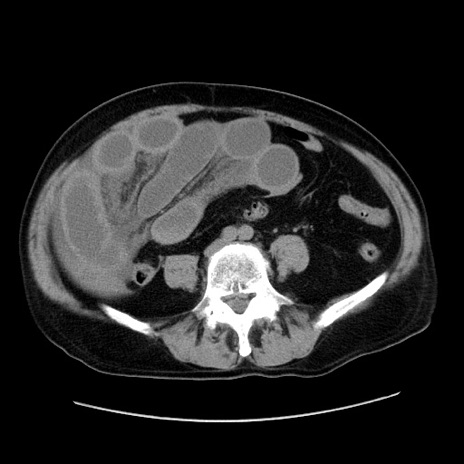

症例30(横断像)

【症例】80歳代男性

【主訴】臍周囲痛

【現病歴】約6時間前から臍下部痛が出現。次第に腹部膨隆・背部痛も生じてきたため来院。背部痛の場所は変化しない。

【身体所見】意識清明、BT 36.3℃、BP  131/87mmHg、P 87bpm、SpO2 100%(RA)、臍周囲自発痛・圧痛あり、反跳痛なし、自発痛部位に一致して板状硬あり、腹部膨隆、腸雑音減弱、CVA tenderness両側陰性。